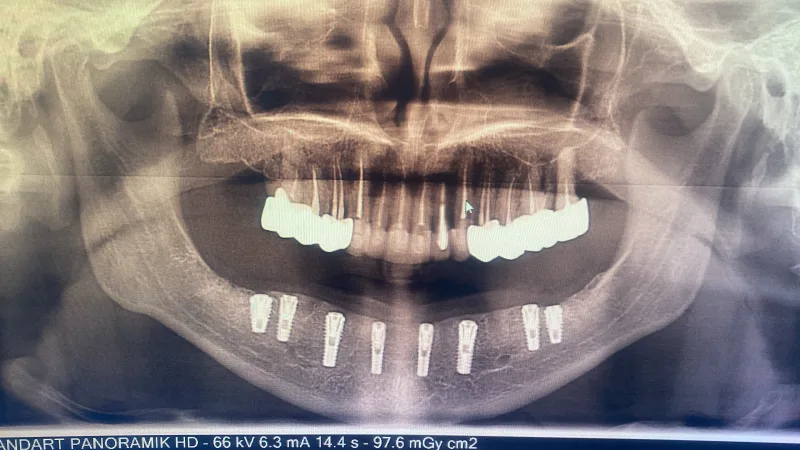

Prothèses et implantations dentaires